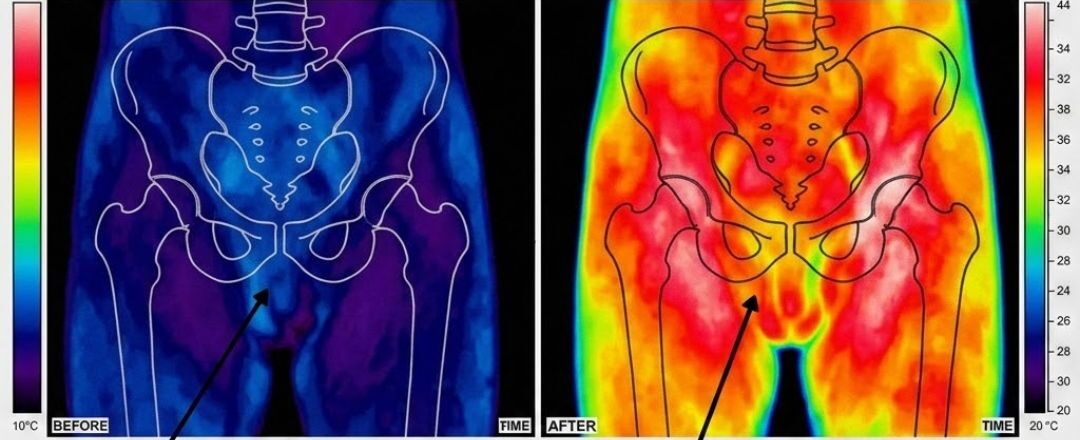

The catch is that regeneration doesn’t happen spontaneously. Peripheral nerves need a signal. They need stimulation — specifically, low-frequency electrical stimulation that mimics the nerve’s own firing pattern and triggers the biochemical cascade that rebuilds the myelin sheath.

It is a precision electrostimulation device. It generates a specific pattern of low-frequency electrical pulses — calibrated to the exact therapeutic parameters of Dr. Mercer’s fourteen-year research programme. Those pulses are delivered through a contact interface to the perineal and penile surface, where they stimulate the cavernous nerve network.

The device does not produce an erection. It does not force a physical response. What it does — over six weeks of daily use — is trigger the neurological repair process that restores the nerve network’s ability to produce an erection on its own, in response to natural arousal.

Phase 1 — Weeks 1 and 2: Activation

Dormant nerve fibres receive targeted stimulation for the first time in years. Most men report a noticeable change within the first ten days. Morning erections absent for years begin to return.Phase 2 — Weeks 3 to 5: Retraining

The nerve network begins rebuilding its response pattern. Spontaneous arousal responses return. Performance confidence begins to rebuild. The anticipatory anxiety that had built over years starts to dissolve.Phase 3 — Week 6 and Beyond: Independence

The circuit is restored. The body responds on its own — without any device, pill or assistance. No more planning ahead. No more waiting for a pill to work. Just a body that functions the way it's supposed to.